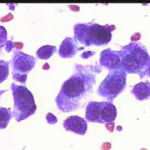

Περιστατικό ασθενούς που παρακολουθείται στο ιατρείο μας από το 1993, τότε ηλικίας 37 ετών, αρχικά λόγω ασυμπατωματικού κυτταρολογικά εμμένοντας έρπητος τραχήλου της μήτρας. Το γεγονός αυτό μας οδήγησε στην διερεύνηση της περιπτώσεως. Η ασθενής επασχε από A.I.D.S.

Είχαμε την ευκαρία να παρακολουθήσουμε ανά 6μηνο γυναικολογικά, κολποσκοιπικά και κυτταρολογικά την γυναίκα από το 1993 μεχρι και το 2008. Από τις εξετασεις αυτές, παρουσιάζουμε χαρακτηριστικές κυτταρολογικές εικόνες . Όι παρακάτω κυτταρολογικές εικονες προέρχονται από την 2η κατά σειρά εξέταση της ασθενούς το 1993. Οι κυτταρολογικές αλλοιώσεις ερπητος συνεχίζουν να υφίστανται.

Ακολουθουν κυτταρολογικές εικονες από τα έτη 1997 - 1998.